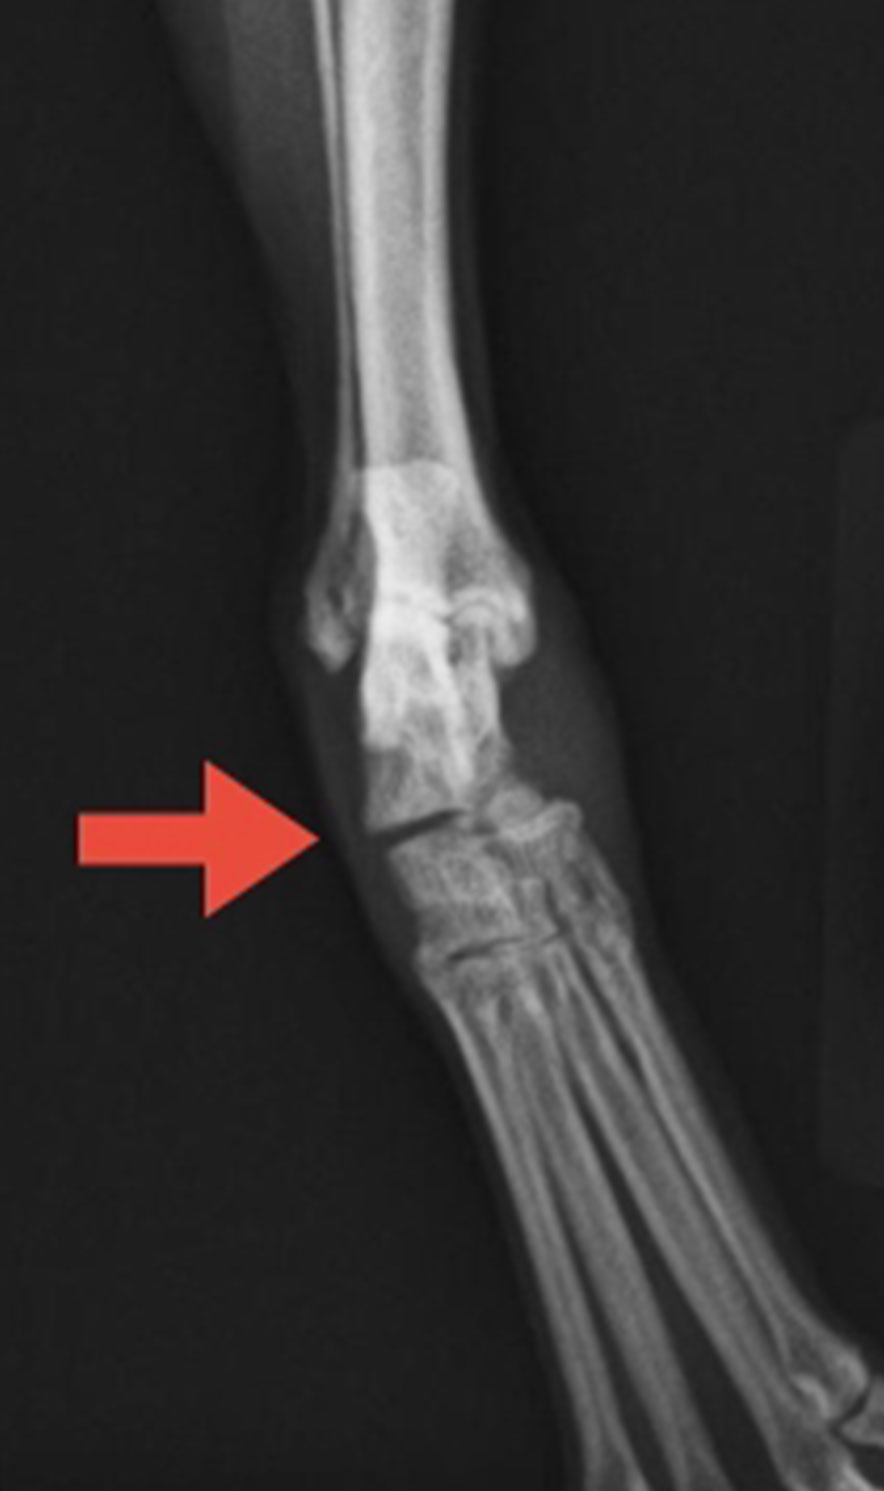

症例紹介(足根関節の脱臼・亜脱臼)

術前 術後

主訴右後肢の跛行(びっこ)

犬種ポメラニアン

年齢4歳5ヶ月

体重4.2kg

性別避妊・メス

右側足根関節の外側の靭帯が一部損傷し、関節の不安定と痛みが生じた症例です。レントゲン写真で関節に意図的に力(ストレス)を加え撮影すると、骨のズレ・不安定が確認されました(赤矢印)。

保存療法では改善が見られず、手術で関節を安定化させました。不安定になった骨同士を、スクリューとワイヤー、ピンで固定しております。